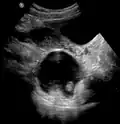

Large ovarian cyst

Dermoid cyst in vaginal ultrasonography -

A complex cyst due to a dermoid as seen on ultrasound -